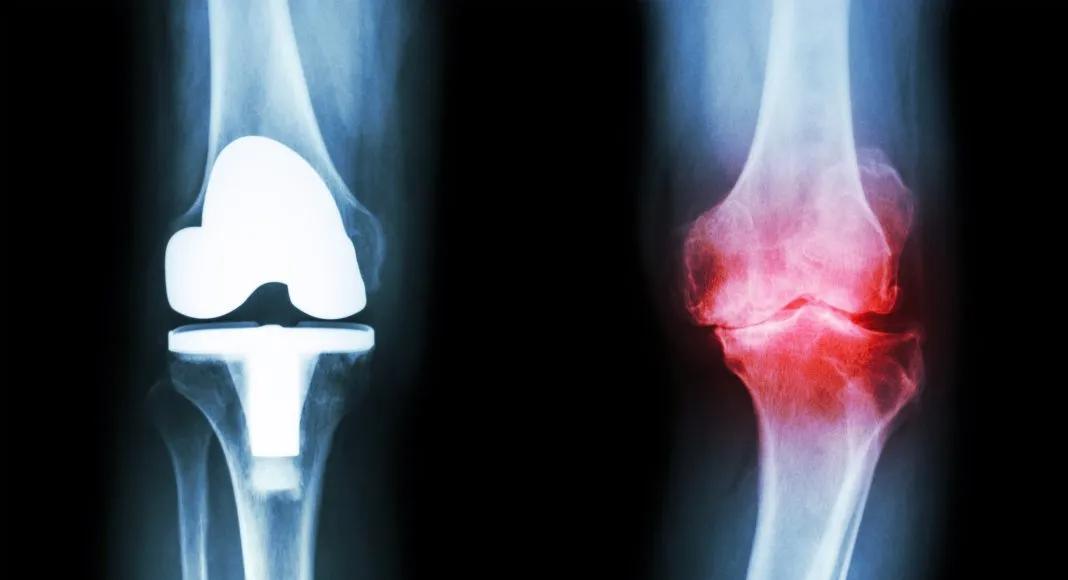

据调查,包括后备军在内的膝骨关节炎患者可以达到2000万— 3000万。 人工关节置换术是晚期病例的标准治疗方法,但这并不是个简单的手术。

骨关节炎(Osteoarthritis,OA)为一种退行性病变,系由于增龄、肥胖、劳损、创伤、关节先天性异常、关节畸形等诸多因素引起的关节软骨退化损伤、关节边缘和软骨下骨反应性增生,又称骨关节病、退行性关节炎、老年性关节炎、肥大性关节炎等。

膝关节炎是骨关节炎中主要的一种,此外,另一项世界卫生组织提供的数据也值得引起我们的关注:50岁以上人群的骨关节病发生率为50%,70岁的老年人发病率高达80%。

膝关节炎的发生一般由膝关节退行性病变、外伤、过度劳累等因素引起。膝关节炎多发于中老年人,是引起老年人腿疼的主要原因。另外,体重过重、不正确的走路姿势、长时间下蹲、膝关节的受凉受寒也是导致膝关节炎的原因。